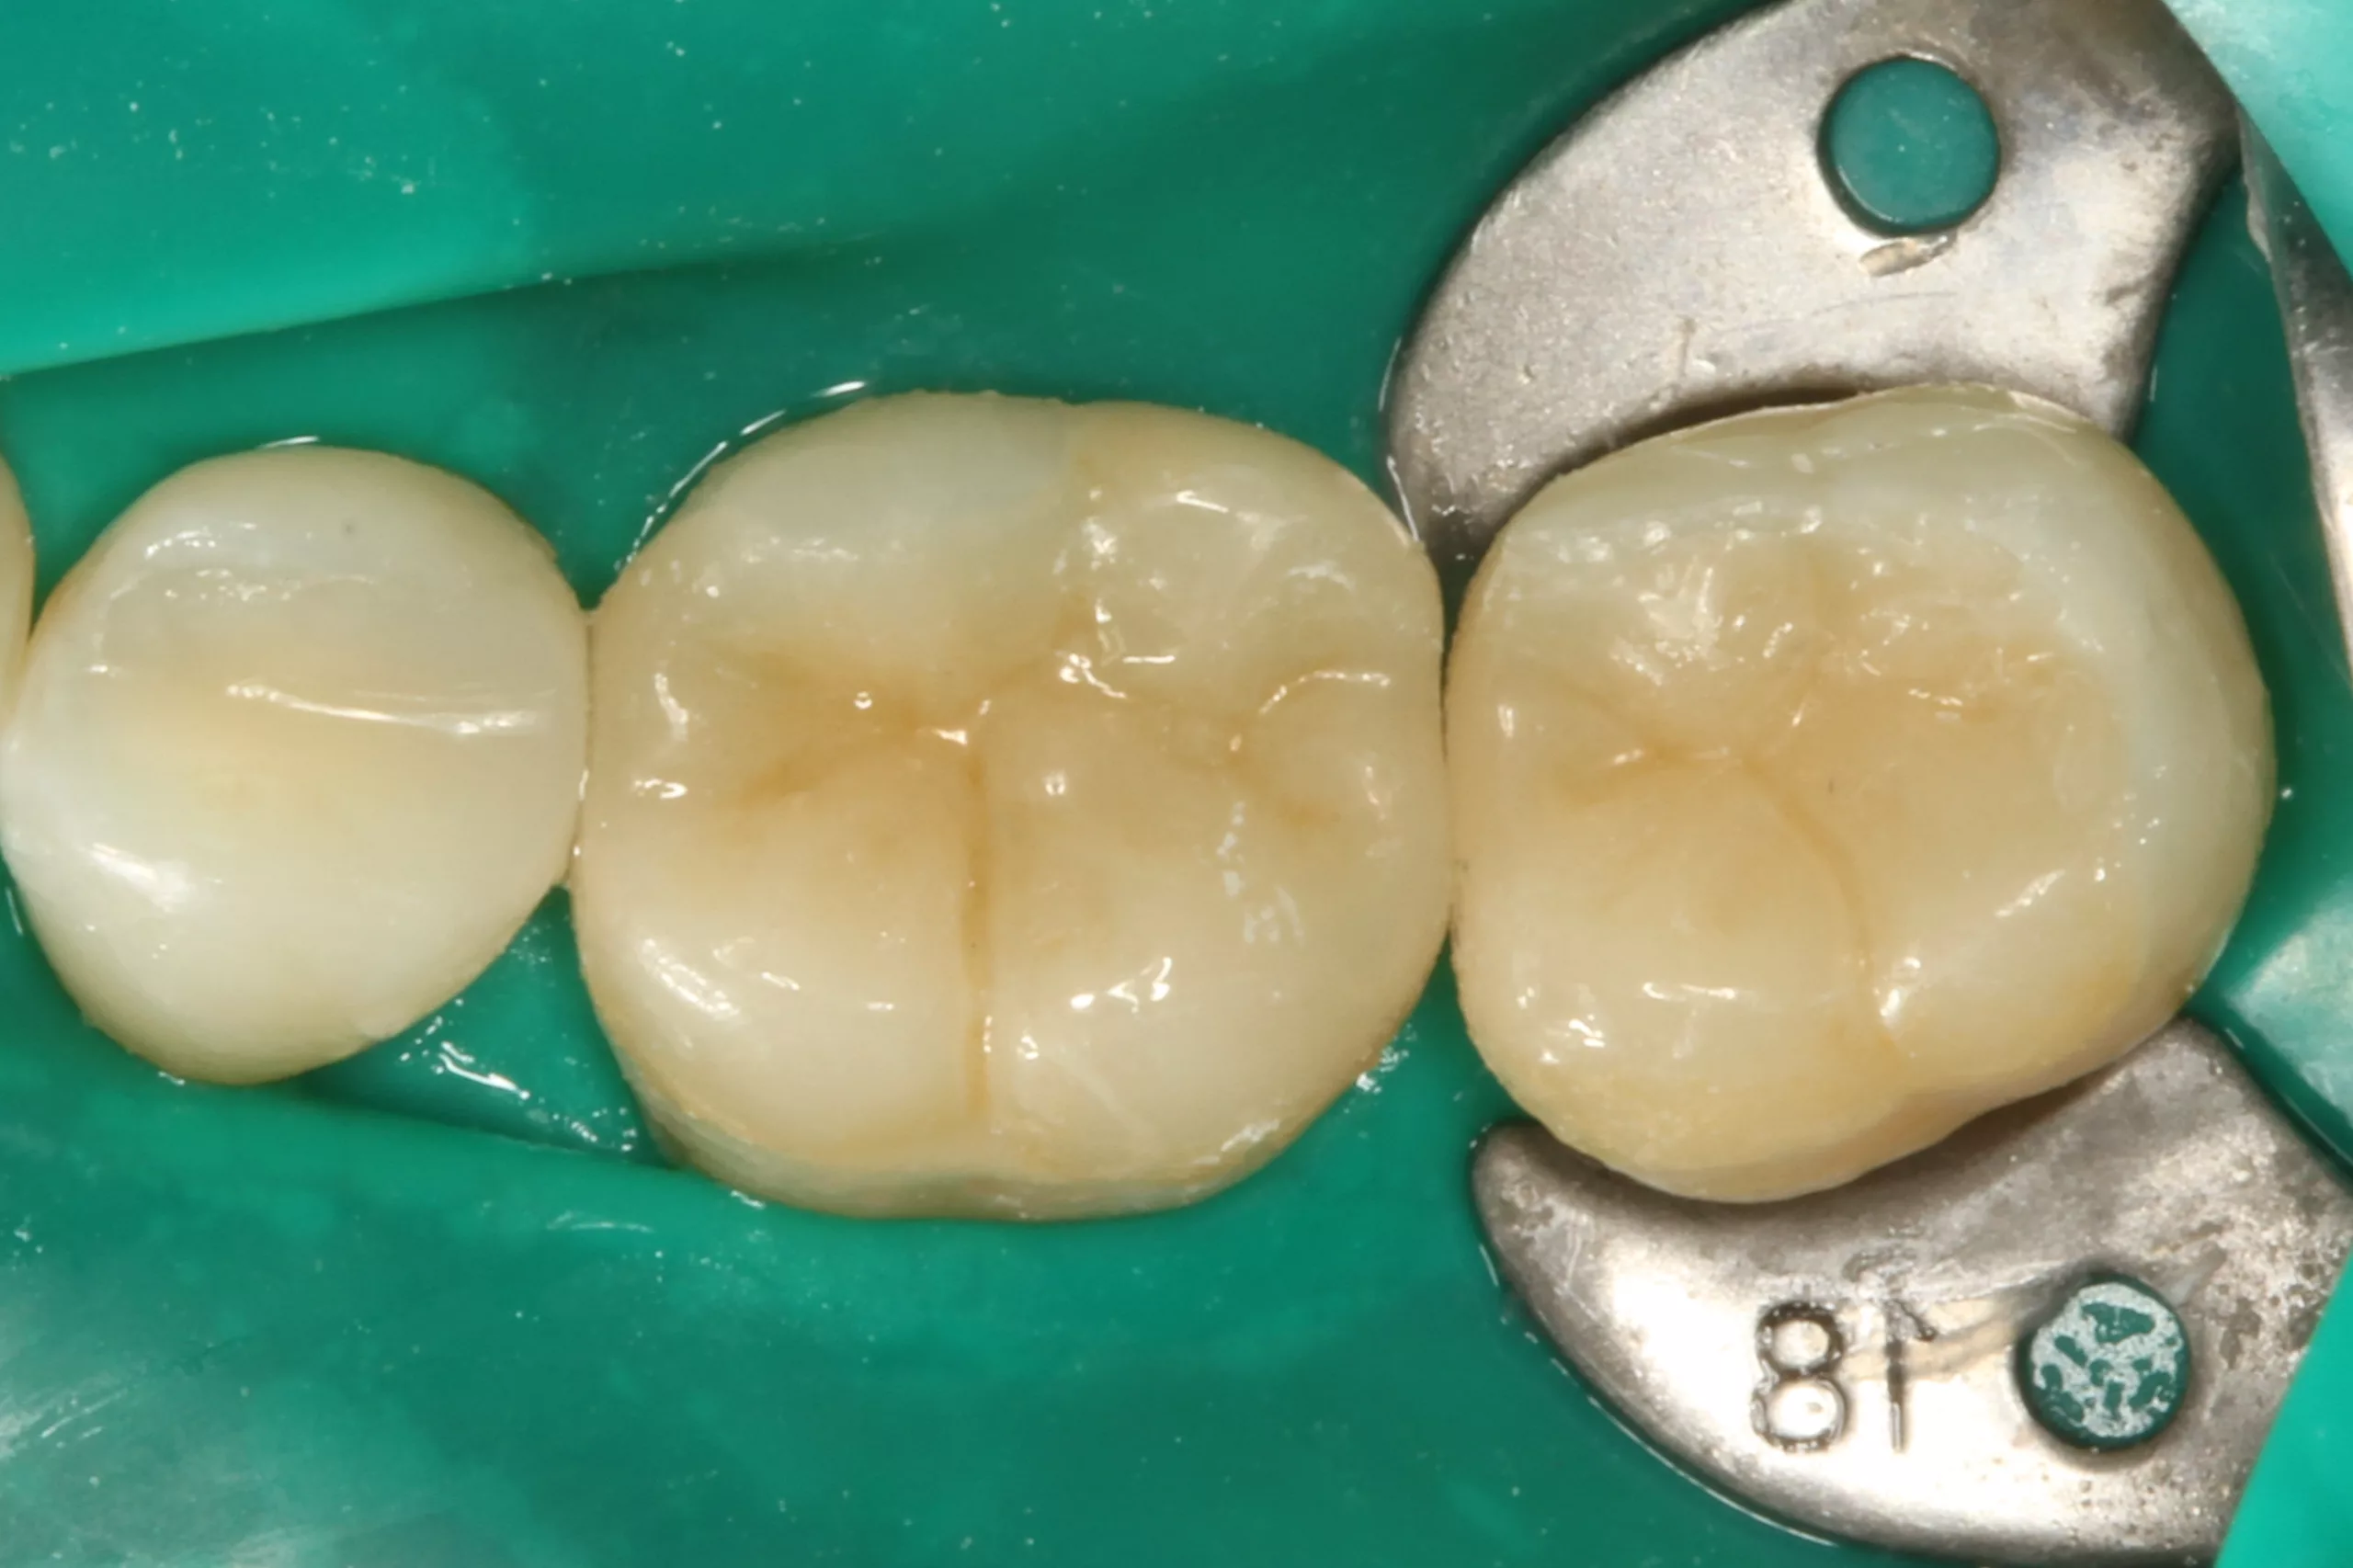

Weiter geht es am Zahn: Die Kontaminationskontrolle ist bei der adhäsiven Befestigung essenziell [84]. Das einfachste Tool – gerade bei adhäsiven Teilkronen – ist die Kofferdamisolierung. Die Abbildung 2 zeigt den isolierten Arbeitsbereich nach Entfernung der Provisorien, der Reinigung der Klebeflächen mit Ultraschall und Bims-Paste (Zircate, Dentsply Sirona) sowie dem Abstrahlen der Kompositfläche an Zahn 46 mit 50 ?m Aluminiumoxid (Rondoflex, KaVo). Die kurze, flügellose Molaren-Kofferdamklammer erleichtert den Zugang zum Approximalraum bei der Versäuberung mit Zahnseide. Da es sich in diesem Bereich um eine adhäsive Kavitätenbodenelevation mit Komposit [66] im Vorfeld der Präparaton und nicht um eine adhäsive Aufbaufüllung handelt, kommt der suffizienten Vorbehandlung auch dieser Klebefläche eine entscheidende Bedeutung zu, um einen Haftverbund zwischen dem Komposit und dem adhäsiven Befestigungssystem zu gewährleisten.

Nach der Schmelzkonditionierung mit dem Phosphorsäuregel und dem ausreichenden Spülen für 15 Sek. ist für eine suffiziente volladhäsive Anbindung ein Benetzungsmittel, ein „Tooth Primer“ erforderlich. Der zu Visalys CemCore gehörende Visalys Tooth Primer ist ein selbstkonditionierender Einkomponenten-Primer, der keiner separaten Lichthärtung bedarf und somit die Ansprüche an die Selbsthärtung des Adhäsivs, die anschließend im Kontakt mit Visalys CemCore abläuft, erfüllt. Die Abbildung 3 zeigt die Einwirkung des Visalys Tooth Primers auf die Präparationsflächen der beiden Zähne 46 und 47. Die Befestigung der Teilkronen erfolgte gleichzeitig mit Visalys CemCore in der Farbe Universal (A2/A3), das vorab direkt auf die Teilkronen und nicht in die Kavitäten appliziert wurde (Abb. 4). Obwohl eine „Tack Cure“-Technik-Option zur Verfügung steht, wurden die Überstände des Befestigungsmaterials mittels Modellierspatel, frischem Bondingpinsel und Zahnseide entfernt. Die im Vergleich zu herkömmlichen Befestigungskompositen etwas höhere Konsistenz und bessere Standfestigkeit (kommt primär der Funktion als Stumpfaufbaukomposit zugute) erleichtert die Überschussentfernung immens, da das Material nicht so schnell unkontrolliert wegfließt. Es erfolgte eine initiale Härtung mittels eines Hochleistungs-LED-Polymerisationsgerätes. Zur Verhinderung der Sauerstoffinhibitionsschicht kann jedes herkömmliche Glyceringel verwendet werden. Alternativ kann die ebenfalls von Kettenbach angebotene Visalys CemCore Try In-Paste zur Anwendung kommen. Obwohl Visalys CemCore eine ausgezeichnete Selbsthärtung aufweist, erfolgte dennoch eine Lichthärtung unter Glyceringel für 20 Sek. pro Fläche. Die Überprüfung der statischen und dynamischen Okklusion darf erst nach Abschluss der Dunkelhärtung vorgenommen werden, damit die adhäsive Integration nicht gestört wird, wenn im Polymerisationsprozess durch Exkursionsbewegungen mechanisch auf die Klebefläche eingewirkt wird.